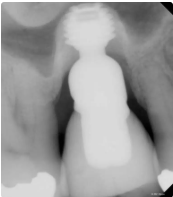

Presentamos el caso de un paciente masculino de 69 años, en el que se realizó la extracción dental seguida de la colocación de un implante Bicon SHORT® de 6,0 x 5,0 mm con pilar de elevación de seno.

El caso se restauró con una corona de pilar integrado (IAC) de 20 mm de longitud y ha sido seguido durante 84 meses.

Este caso destaca no solo por la estabilidad a largo plazo del implante corto, sino también por mostrar de forma radiográfica la aplicación de la Ley de Wolff: el hueso se adapta y se refuerza en respuesta a la carga funcional.